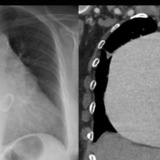

Giant RA CT

Date: 01/07/2012

Views: 2625